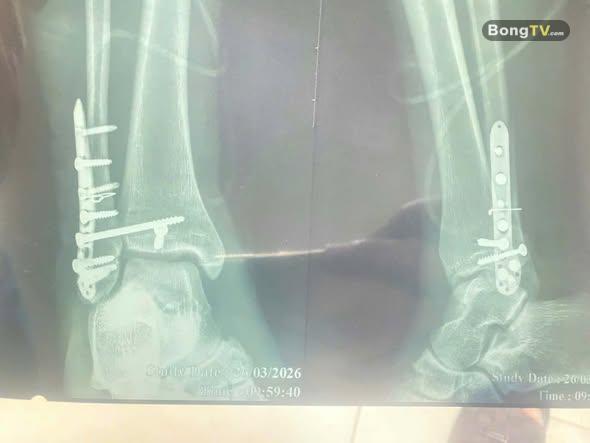

Ca phẫu thuật của cầu thủ Văn Dũng FC MỎ THỔ đã thành công. Xin chúc cho Văn Dũng sẽ mau bình phục và sớm trở lại